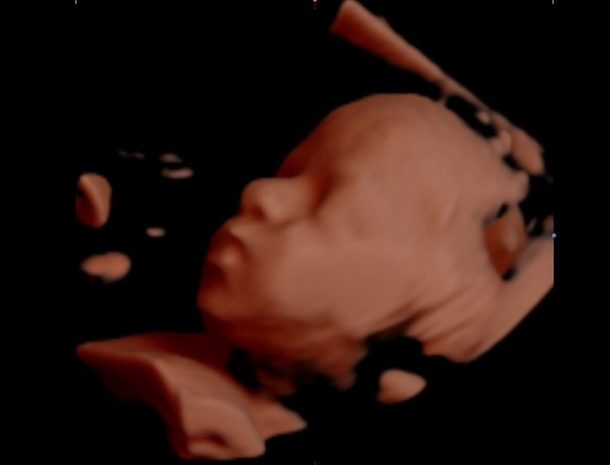

Balıkesir'de 4 boyutlu ultrasonla çalışan Operatör Dr. Alaattin Kaçar, 4 boyutlu görüntüleme olarak bilinen bu ultrasonda, bilgisayar programlarıyla ışık ve gölgelendirme yapabildiğini belirterek, böylece daha iyi görüntü alınabildiğini anlattı.

Kaçar, bu sistemin iyi kullanılması durumunda güzel sonuç verdiğini vurgulayarak, "Balıkesir'de aldığımız sonuçlar, cihazı üreten firmanın ilgisi çekiyor. Bizden aldıkları görüntüleri, yurt dışındaki panel ve konferanslarda kullanıyorlar. Hatta firma, bizim görüntülerle tanıtımını yapıyor" dedi.

Bu yeni teknolojiyle bebeğin daha iyi görülebildiğini, anne karnındaki durumunun, sağlığının daha iyi değerlendirilebildiğini dile getiren Kaçar, "Bebeğin hareketleri daha iyi görülebiliyor. Hekimler olarak aslında genellikle iki boyutlu değerlendirme yaparız, kesitler alarak bebeği inceleriz ancak bu tür sistemlerde görüntü kaliteleri çok yüksek. Bizim daha net tanı koymamızı güçlendiriyor.

Aileler, bebeklerini, kafalarında canlandırıyor, anne karnında görebiliyor. Aileler artık, fotoğraf albümü oluşturmak için doğumu beklemeden anne karnında başlıyor" dedi.

Yedinci aydan itibaren bebeklerde yavaş yavaş tüylenmeler görülüyor. Cildi normal bebek halini alıyor. Sekizinci ve dokuzuncu ayda bebek doğduğu pozisyona geliyor. Doğmuş bebeğin her türlü özelliğini taşıyor. Bu aylarda hızlı kilo alıyor. Dokuzuncu ayda doğumdan sonra gördüğünüz bebeği anne karnında birebir görüyorsunuz."